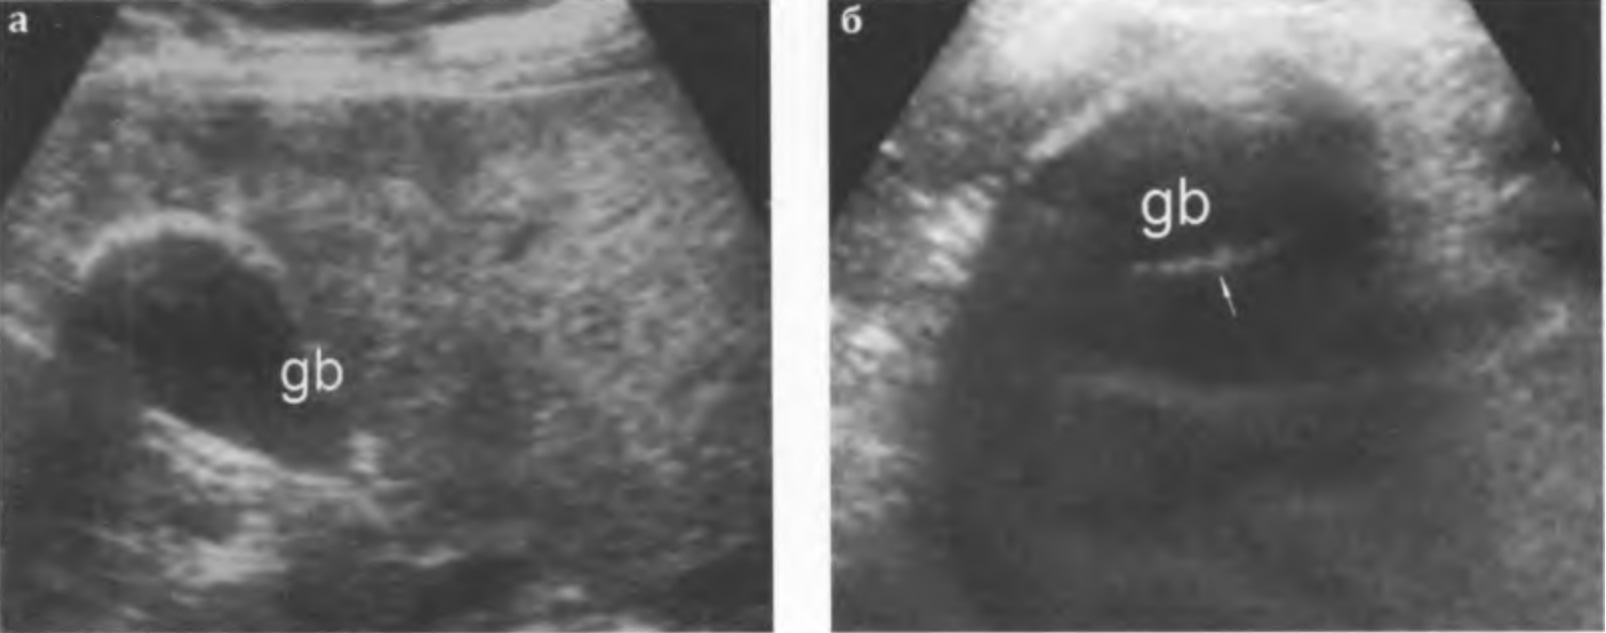

Гиалинокальциноз - изменение стенки пузыря, чаще возникающее после перенесенного тяжелого приступа острого холецистита. Характеризуется отложением пластов извести в мышечной оболочке или накоплением кристаллов солей в синусах Рокитанского-Ашоффа с формированием так называемого "фарфорового" пузыря. Стенка имеет значительно повышенную эхогенность на ограниченном или достаточно протяженном участке. При этом желчный пузырь визуализируется как кольцевидная гиперэхогенная структура с неинтенсивной дистальной и широкими латеральными тенями, причем сохраняется возможность визуализировать центральную часть задней стенки пузыря (рис. 3.21а,б). Акустическая тень образуется именно за стенкой пузыря, камней в его просвете может не быть.

Рис. 3.21 а, б. "Фарфоровый" желчный пузырь (значительное повышение эхогенности стенки желчного пузыря (gb), за стенкой определяется акустическая тень):

а - акустическая тень формируется за частью стенки в области дна желчного пузыря;

б - за всей передней стенкой формируется широкая акустическая тень с более выраженными латеральными тенями, что позволяет визуализировать часть задней стенки пузыря (стрелка).